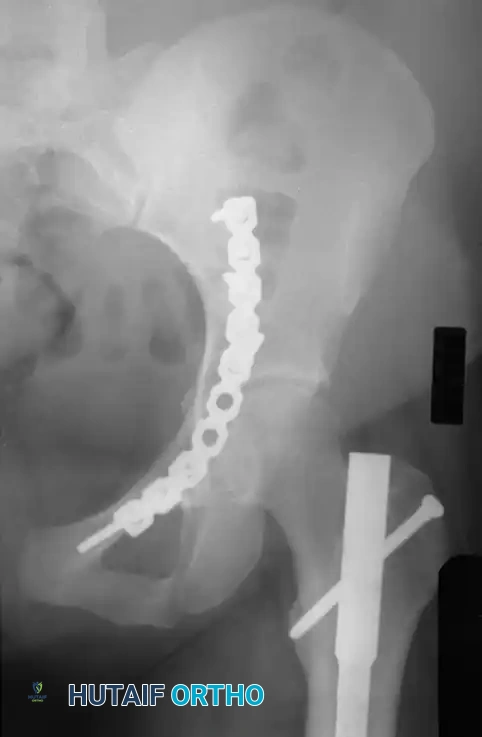

Fig. 53-3 Transverse acetabular fracture with true central fracture-dislocation; intrapelvic femoral head can become locked between superior and inferior fracture fragments.

In these scenarios, the femoral head may become incarcerated between the superior and inferior fracture fragments, rendering closed reduction impossible.

Fig. 53-4 Anteroposterior pelvic radiograph ( A ) and CT scan ( B ) of irreducible hip dislocation with posterior wall acetabular fracture. Posterior wall fragment is incarcerated, blocking reduction.

If closed reduction under conscious sedation or general anesthesia fails, urgent open reduction is mandated. A rapid, fine-cut (2-3 mm) Computed Tomography (CT) scan should be obtained to identify the incarcerating fragment—often a rotated posterior wall fragment or an intra-articular osteochondral loose body. Prolonged dislocation exponentially increases the risk of femoral head osteonecrosis and irreversible sciatic nerve ischemia.